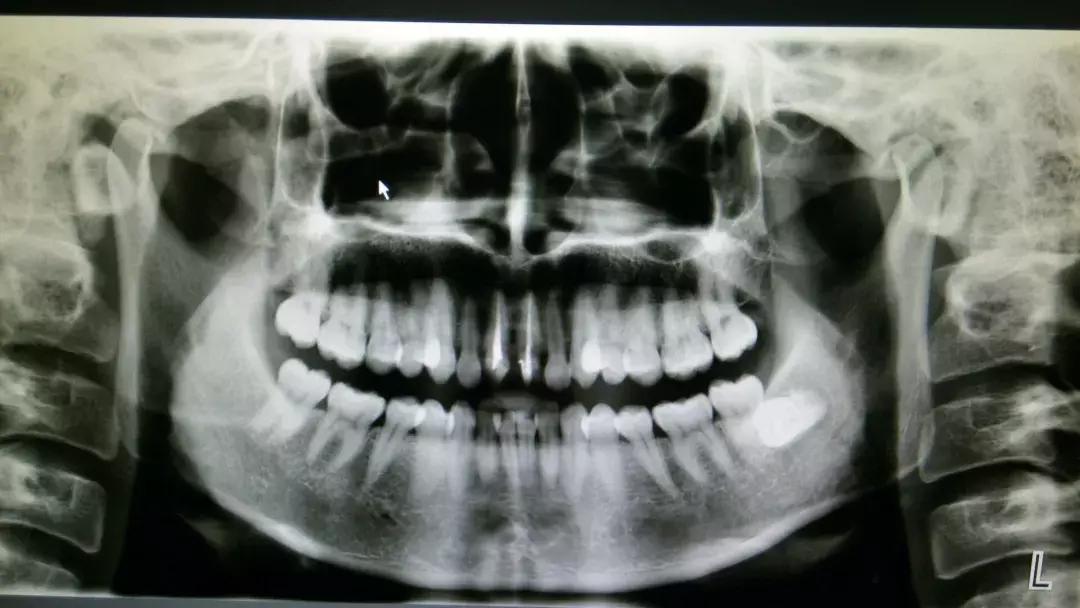

智齿因阻生疑为不明原因神经痛

或可疑病灶牙时

阻生智齿和神经的关系↓

对待这种「骑」在神经上的智齿要以医生建议为主,即使拔也一定要选择微创拔哦。这个危险距离,一锤子下去,神经可就很难保住了。